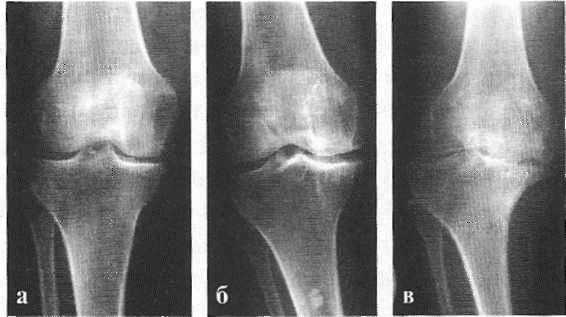

Классификация и стадии развития артроза коленных суставов

Независимо от причины возникновения выделяют три стадии заболевания гонартроза, или деформирующего артроза коленного сустава.

Первая стадия заболевания характеризуется первичными изменениями в гиалиновом хряще. [12] [18] Костные структуры не затрагиваются. Во внутрикостных сосудах и капиллярах нарушается кровоснабжение. Становится сухой поверхность хряща, и он утрачивает свою гладкость. Если заболевание сопровождается постоянным напряженным синовитом, то развивается киста Бейкера (грыжевое выпячивание капсулы сустава подколенной области). [15] После значительной нагрузки на сустав возникают тупые боли. Возможна небольшая отечность, которая проходит после отдыха. Деформации нет.

Гонартроз, II стадия

На второй стадии хрящевая прослойка резко истончается, а местами и вовсе отсутствует. [22] Появляются остеофиты по краям суставных поверхностей. Изменяются качественные и количественные характеристики синовиальной жидкости сустава — она становится гуще, более вязкой, что приводит к ухудшению питающих и смазывающих свойств. [14] [16] Боли более продолжительные и интенсивные, часто при движении появляется хруст. Отмечается незначительное или умеренное ограничение движений и небольшая деформация сустава. Прием анальгетиков помогает снять болевой синдром.

Гонартроз, III стадия

Отсутствие хряща на большинстве поражённых участков, выраженный склероз (уплотнение) кости, множество остеофитов и резкое сужение или отсутствие суставной щели. [8] [15] Боли практически постоянные, походка нарушена. Подвижность резко ограничена, заметна деформация сустава. Препараты НПВС, физиопроцедуры и другие стандартные методы лечения артроза коленного сустава неэффективны. [11]

В подавляющем большинстве случаев достаточно осмотра и рентгенограммы коленного сустава в двух проекциях (прямой и боковой). [2] [19] Клинические данные и снимки позволяют определить стадию заболевания.

На ранних стадиях заболевания, при незначительных изменениях в костной ткани, рентгенологическое обследование не настолько ценно. [5] [8] На этом этапе гонартроз возможно диагностировать благодаря артроскопии. [5] [8] Точность метода очень высока, останавливать может только его инвазивный характер и цена.

- Артроз коленного сустава 1 степени - появляется размягчение хряща, можно прощупать на поверхности колена. Не видно на рентгеновском снимке.

- Артроз коленного сустава 2 степени - хрящ начинает стираться и на снимке можно заметить сужение суставной щели.

- Артроз коленного сустава 3 степени - проявляются остеофиты, лечение более затруднительно. Сложно отличить от 2-ой степени.

- Артроз коленного сустава 4 степени - кости соприкосаются друг с другом, увеличивается остеофиты, происходит искажение сустава.